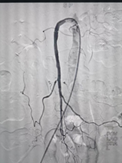

对此,普外科医师团队与多学科开展紧急会诊,并制定出最佳手术方案,决定为患者开展介入手术治疗致命肠系膜上动脉栓塞。在征求患者及家属同意后,普外科团队立即启动“绿色通道”,由副主任医师郭陵主刀,紧急为患者实施介入手术(肠系膜上动脉吸栓+肠系膜上动脉球囊扩张+肠系膜上动脉支架置入术),手术过程顺利。

术中取栓前后肠系膜上动脉造影对比

经过介入手术,患者堵塞的肠系膜上动脉即时完全开通,且患者腹部疼痛症状明显改善。